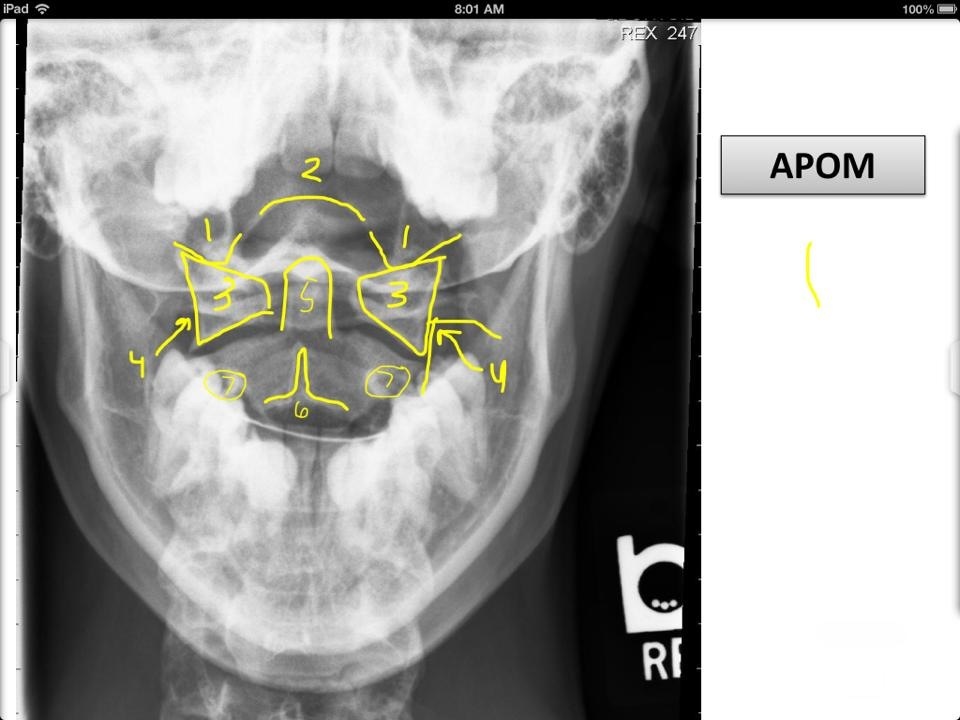

8

2

9

3

10

4

11

5

12

6

13

7